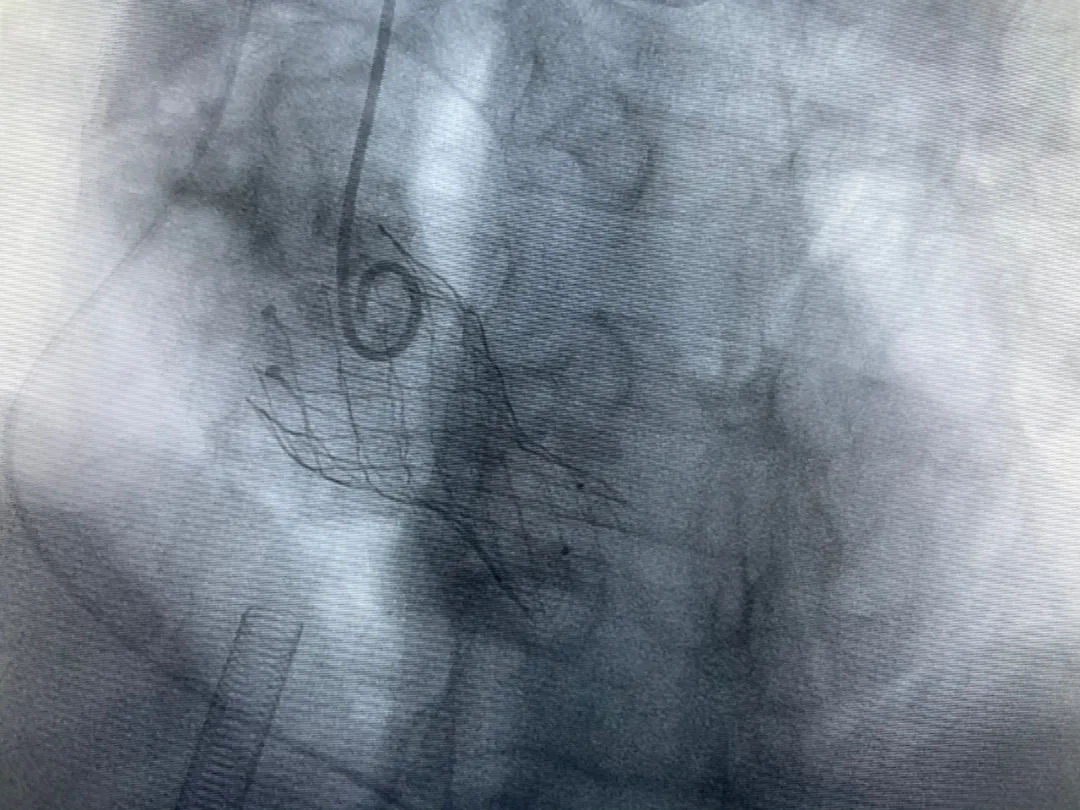

結(jié)合老人病情特點(diǎn):年齡高、室壁厚、左室腔小、瓣膜鈣化嚴(yán)重,術(shù)中球囊擴(kuò)張和瓣膜釋放過(guò)程有循環(huán)崩潰可能;為降低此種風(fēng)險(xiǎn)、最大程度提高手術(shù)成功率,張金洲副院長(zhǎng)在術(shù)前組織了由楊金保博士帶領(lǐng)的TAVR團(tuán)隊(duì)多次反復(fù)溝通、討論,制定了各種應(yīng)急處理方案。最終經(jīng)過(guò)TAVR團(tuán)隊(duì)的默契配合,手術(shù)歷時(shí)2小時(shí),用20#球囊預(yù)擴(kuò)張后順利植入23#主動(dòng)脈瓣生物瓣膜,再次后擴(kuò)后主動(dòng)脈根部造影顯示:人工主動(dòng)脈瓣生物瓣位置良好,瓣葉開閉正常;冠脈顯影良好。經(jīng)食道超聲顯示:主動(dòng)脈瓣葉活動(dòng)度良好,主動(dòng)脈跨瓣壓差約35mmHg,未見瓣周漏及明顯返流。出手術(shù)室前老人便已蘇醒,自訴憋悶癥狀完全消失。